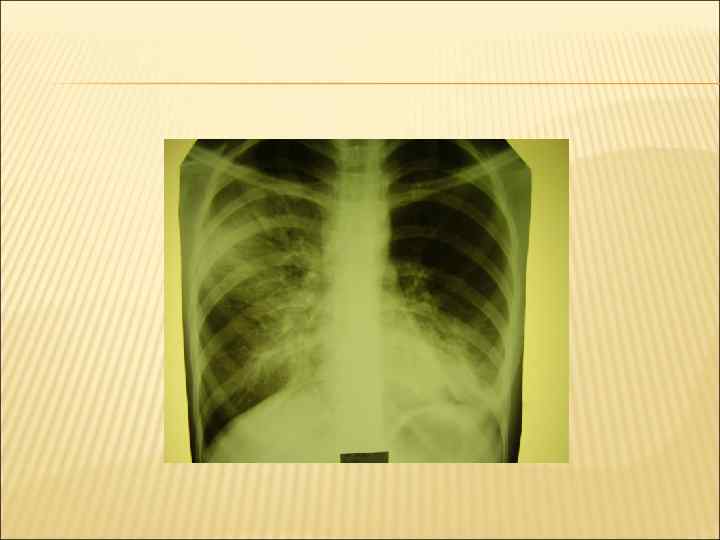

СИНДРОМ КРУПНООЧАГОВОЙ ИНФИЛЬТРАЦИИ Кашель, учащенное, затрудненное дыхание (одышка). Повышение температуры тела, Ухудшение самочувствия, слабость, изменение поведения Те же симптомы что и при мелкоочаговой, но они более выражены. Большие зоны притупления легочного звука.

Голосовое дрожание над очагом – усилено Бронхиальное дыхание. Крепитация. Бронхофония - усилена. На фоне измененного легочного рисунка массивные области затемнения (иногда целая доля легкого)